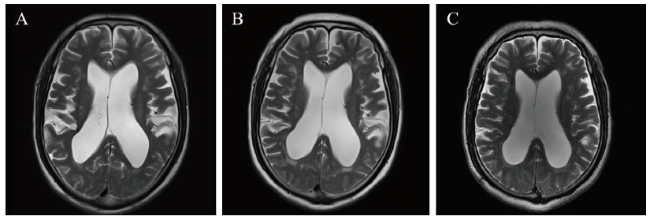

图2 一例AAV肾损害合并交通性脑积水患者的肾脏病理结果

注:A (PAS染色,×40)示新旧不等的新月体形成,肾小管小灶性萎缩,间质纤维化;B(PAS染色,×200)示肾小球新月体形成,肾小管小灶性萎缩,余肾小管上皮细胞颗粒变性及空泡变性,灶性上皮细胞刷状缘脱落、细胞扁平;C(免疫荧光,×200)示IgA(+),局灶性球性分布,颗粒状沉积于系膜区。

2. 肾活检病理

2019年4日4日行肾穿刺活检(图2),光镜下冰冻切片中可见3个肾小球,其中1个新月体形成;石蜡切片中可见20个肾小球,其中2个球性硬化、5个细胞性、7个细胞纤维性、2个小细胞性、1个小细胞纤维性新月体形成,少数肾小球球囊壁于新月体处破坏,与间质分界不清。残存肾小球系膜细胞及基质轻度增生,内皮细胞未见增生。肾小管小灶性萎缩(约20%),余肾小管上皮细胞颗粒变性及空泡变性,灶性上皮细胞刷状缘脱落、细胞扁平,可见部分红细胞管型。肾间质灶性水肿、小灶性纤维化伴单个核细胞浸润。小动脉内膜纤维性增厚,细动脉多处中度透明变性。免疫荧光示4个肾小球IgA(+),局灶性球性分布,颗粒状沉积于系膜区,IgG、IgM、C3、C1q、Fg均阴性。特殊染色示刚果红(-)。免疫组织化学染色结果示间质中的浆细胞CD138、IgG、IgG4均(+),IgG4+/IgG+ < 40%。病理诊断:①新月体肾炎,考虑为Ⅲ型;②合并IgA肾病可能。